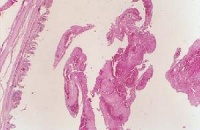

喉痛、声嘶、喉喘鸣和呼吸困难,并可伴发热恶寒,咽喉疼痛,喉镜下可见粘膜呈深红色水肿、表面发亮,喘鸣,声嘶,呼吸困难,甚则窒息,喉镜下可见喉粘膜弥漫性水肿,苍白。